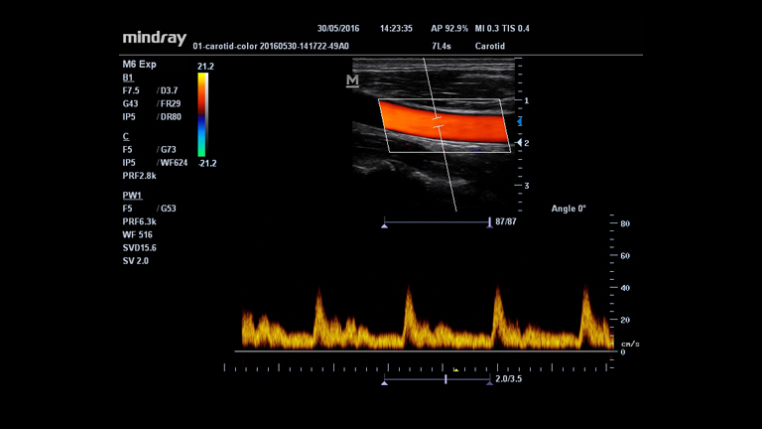

Auto IMT (automatyczny pomiar kompleksu Intima-Media)

Automatyczny pomiar grubości kompleksu Intima-Media na przedniej i tylnej ścianie naczynia, zapewniający precyzję badania stanu tętnicy szyjnej.

Smart Track (Inteligentny obrys)

Unikalna funkcja Firmy Mindray: Ciągłe śledzenie naczynia z przepływem w trybie Dopplera kolorowego wraz z jednoczesną optymalizacją pozycji bramki (ROI) Dopplera kolorowego i kąta ustawienia bramki (pochylenie wiązki ultradźwiękowej) podczas skanowania w czasie rzeczywistym.